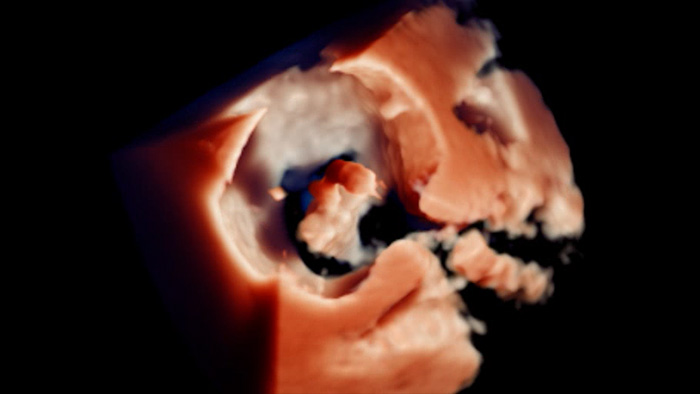

TrueVue du rendu 3D Zoom pour l’appendice auriculaire gauche avec visualisation MultiVue

Visualisation TrueVue de la réparation mitrale bord à bord